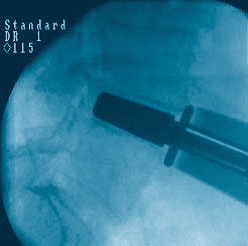

prodisc L Gallery

Click to enlarge image